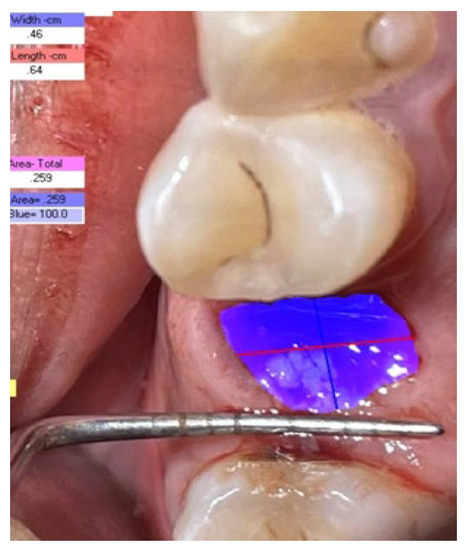

2.3.2. Digital Planimetry Method